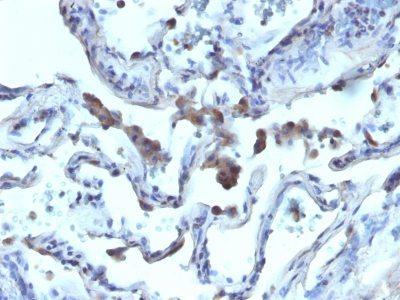

This antibody recognizes a protein of 42 kDa, which is identified as Alpha-methylacyl-CoA Racemase (AMACR), also known as p504S. It is an enzyme that is involved in bile acid biosynthesis and beta-oxidation of branched-chain fatty acids. AMACR is essential in lipid metabolism. It is expressed in cells of premalignant high-grade prostatic intraepithelial neoplasia (HGPIN) and prostate adenocarcinoma. The majority of the carcinoma cells show a distinct granular cytoplasmic staining reaction. AMACR is present at low or undetectable levels in glandular epithelial cells of normal prostate and benign prostatic hyperplasia. A spotty granular cytoplasmic staining is seen in a few cells of the benign glands. AMACR is expressed in normal liver (hepatocytes), kidney (tubular epithelial cells) and gall bladder (epithelial cells). Expression has also been found in lung (bronchial epithelial cells) and colon (colonic surface epithelium). AMACR expression can also be found in hepatocellular carcinoma and kidney carcinoma. Past studies have also shown that AMACR is expressed in various colon carcinomas (well, moderately and poorly differentiated) and overexpressed in prostate carcinoma.

Higher concentration may be required for direct detection using primary antibody conjugates than for indirect detection with secondary antibody|Immunohistology formalin-fixed 1:50-1:100|Staining of formalin-fixed tissues requires boiling tissue sections in 10 mM Tris with 1 mM EDTA, pH 9.0, for 10-20 min followed by cooling at RT for 20 minutes|Optimal dilution for a specific application should be determined by user